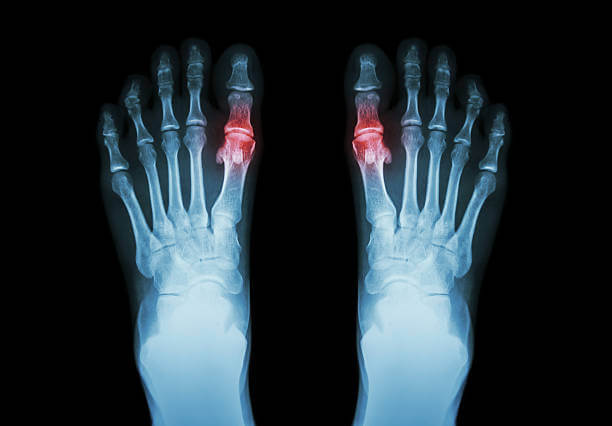

혈액검사만으로 부족할 경우, 관절 초음파와 영상 진단이 중요한 역할을 합니다. 관절 초음파는 요산 결정이 관절 내부나 연부 조직에 쌓인 모습을 직접 확인할 수 있어 조기 진단에 특히 유용합니다. 이 방법은 비침습적이고 반복적으로 시행할 수 있어, 부산 지역 전문병원에서도 자주 활용됩니다. 만성 통풍 환자의 경우, X-ray 촬영에서 관절 간격의 좁아짐, 골 미란, 관절 변형 같은 소견이 나타날 수 있습니다. CT나 MRI 검사는 더 정밀하게 관절 내부와 주변 조직의 상태를 보여주며, 통풍석이나 관절 손상의 범위를 확인하는 데 효과적입니다. 또한 확진을 위해 관절액 검사(관절 천자)가 시행되기도 합니다. 이는 통풍이 의심되는 관절에서 관절액을 채취하여 현미경으로 관찰하는 검사입니다. 백혈구 안에서 바늘 모양의 요산 결정이 발견된다면 통풍으로 확진할 수 있습니다. 이 검사는 다소 침습적일 수 있지만, 임상적으로는 가장 확실한 진단 방법으로 꼽힙니다.